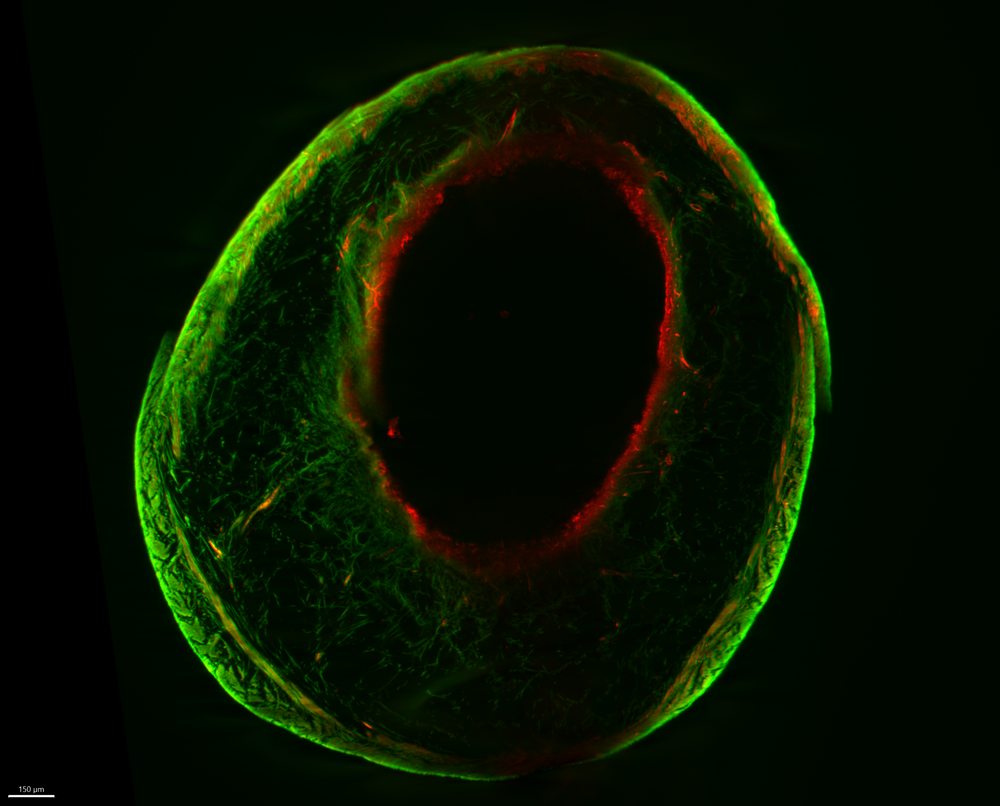

Fluorescent microscopic image showing a circular tissue structure with a dark central opening, outlined by red fibres and surrounded by a green outer layer

The Olive – entered by Dr Jess Trundle, Research Fellow This image shows a mouse bladder inflated to reveal its layered structure. Fluorescent dyes highlight different collagen networks that help the bladder stretch and contract. Studying this structure helps researchers understand bladder function and disorders, which is crucial for improving treatments for conditions affecting bladder control in children and adults.